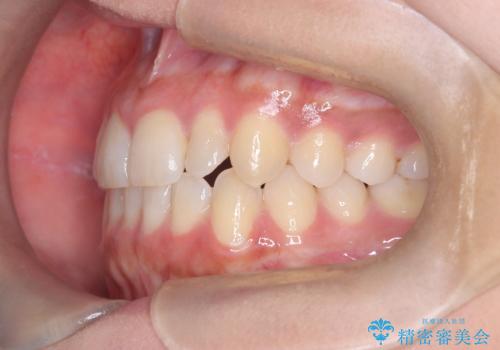

反対咬合と前歯のガタガタを非抜歯で改善

- 患者様は、上下の前歯のガタガタと反対咬合(下の歯が上の歯より前に出ている状態)を主訴として来院されました。診断の結果、抜歯を行わずに治療を進めるため、臼歯を遠心移動させてスペースを作り、IPR(インタープロキシマルリダクション)で歯間を調整する治療計画を立てました。インビザラインを使用して、透明で目立たない矯正装置により、歯列を整えながら噛み合わせも改善することを目標としました。

非抜歯での治療では、限られたスペースの中で効率的に歯を動かす必要があります。本症例では、臼歯を後方に移動させる遠心移動を行い、歯列のガタガタを改善しました。また、IPRを適切に行うことでスペースを確保し、歯根や歯肉への負担を最小限に抑えながら治療を進めました。インビザラインを使用することで、治療中も目立ちにくく、患者様の日常生活への影響を軽減しました。結果として、抜歯を行わずに美しい歯並びと自然な噛み合わせを実現し、患者様には大変満足していただけました。